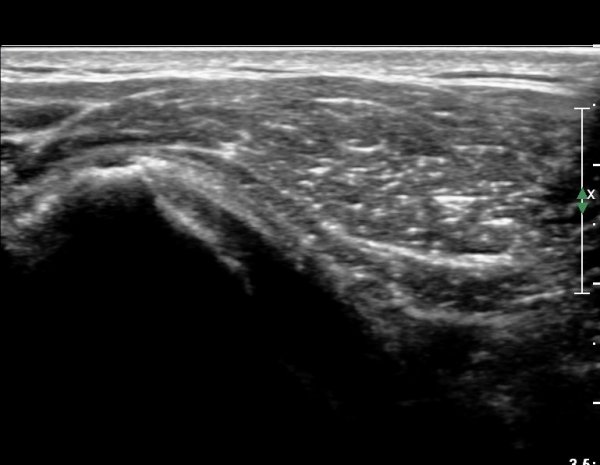

°ß°©ÇÏ±Ù°Ç ÇϺΠÁ¾´Ü¸é°Ë»ç¿Í Ⱦ´Ü¸é°Ë»ç °ß°©Çϱٰdz»  ¼®È¸È­ À½¿µÀÌ  °üÂûµÈ´Ù(»çÁø 3, 4).

°ß°©ÇÏ±Ù°Ç È¾´Ü¸é°Ë»ç»ó ¼Ò°áÀý ÇÊÁú°ñº¯È­¿Í °ß°©ÇÏ±Ù°Ç Áߺο¡ °í¿¡ÄÚ µ¢¾î¸®°¡ °üÂûµÇ°í

¼®È¸ À§ÂÊ(¸Ó¸®ÂÊ)ÀÇ ÈûÁÙÀÇ Àú¿¡ÄÚ º¯È­°¡ °üÂûµÈ´Ù(»çÁø 4, 5).